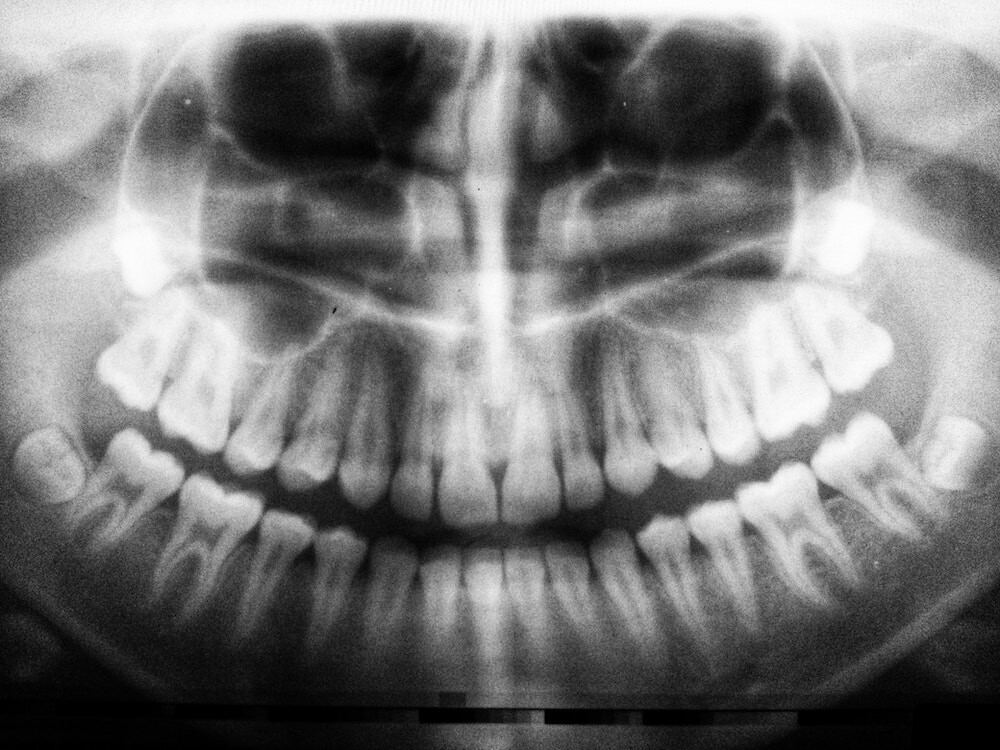

One of the most common places for resorption to occur is in the jawbone.

WHAT CAUSES JAWBONE RESORPTION?

One of the main reasons for jawbone resorption is the loss of teeth.

When the root is removed, your jawbone no longer receives the stimulus and pressure of chewing. This causes your body to believe that it no longer requires the same bone density in that area.

When a tooth is extracted or lost, up to 25% of bone density can be lost in the first year — and the process continues. Jawbone loss causes your face to shrink, which may make you appear older than you actually are.